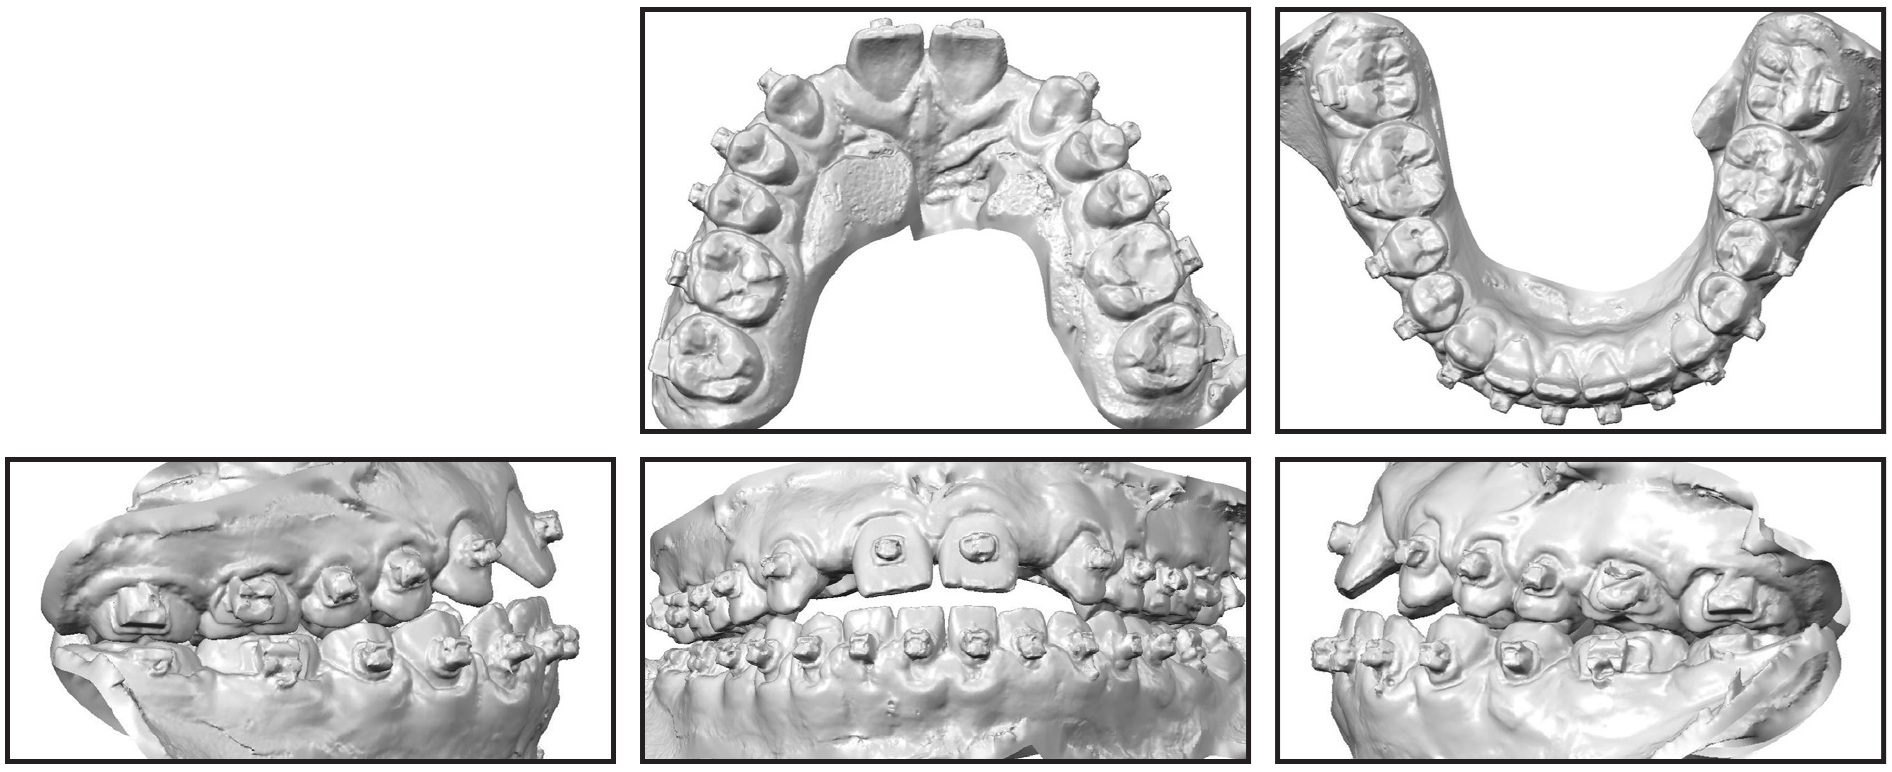

When a patient in the middle of orthodontic treatment visits your practice for a second opinion, it can be awkward if you disagree with the current orthodontist’s plan. Such was the conversation with this 17-year-old male patient and his parents. The patient presented in fixed Damon* appliances that he had worn for nearly two years, in an attempt to create space for the restoration of congenitally missing maxillary lateral incisors (Fig. 1A). He exhibited an anterior open bite and inadequate space for implants, and he reported that his current orthodontist was recommending the extraction of four premolars to correct the occlusion.

Clinical evaluation found a symmetrical face with well-balanced vertical thirds, a straight profile, and a normal nasolabial angle. The patient had inadequate maxillary incisor display at rest (0mm) and in smiling. He presented a 1mm anterior open bite, constricted arches, and a minimum cross-sectional airway area of 172.1mm2. The maxillary posterior teeth were tipped buccally and the mandibular posterior teeth were tipped lingually, indicating a transverse skeletal discrepancy. There was 6.4mm of space for the congenitally missing maxillary right lateral incisor and 5.5mm for the left lateral incisor, but the prosthodontist requested 7mm of space for restoration of each tooth (Fig. 1B).

All third molars were present and unerupted. Cephalometric analysis indicated a mild skeletal Class III pattern (Wits appraisal = −4.1) with a vertical growth pattern (MP-SN = 38.6°), proclined maxillary incisors (U1-NA = 34.2°), and normally inclined mandibular incisors. The upper and lower lips were 1-2mm behind the Ricketts E-line.

Fig. 1 17-year-old male patient with mild skeletal Class III pattern, congenitally missing upper lateral incisors, constricted arches, and anterior open bite after treatment by previous orthodontist (continued in next image).

Fig. 1 (cont.) 17-year-old male patient with mild skeletal Class III pattern, congenitally missing upper lateral incisors, constricted arches, and anterior open bite after treatment by previous orthodontist.